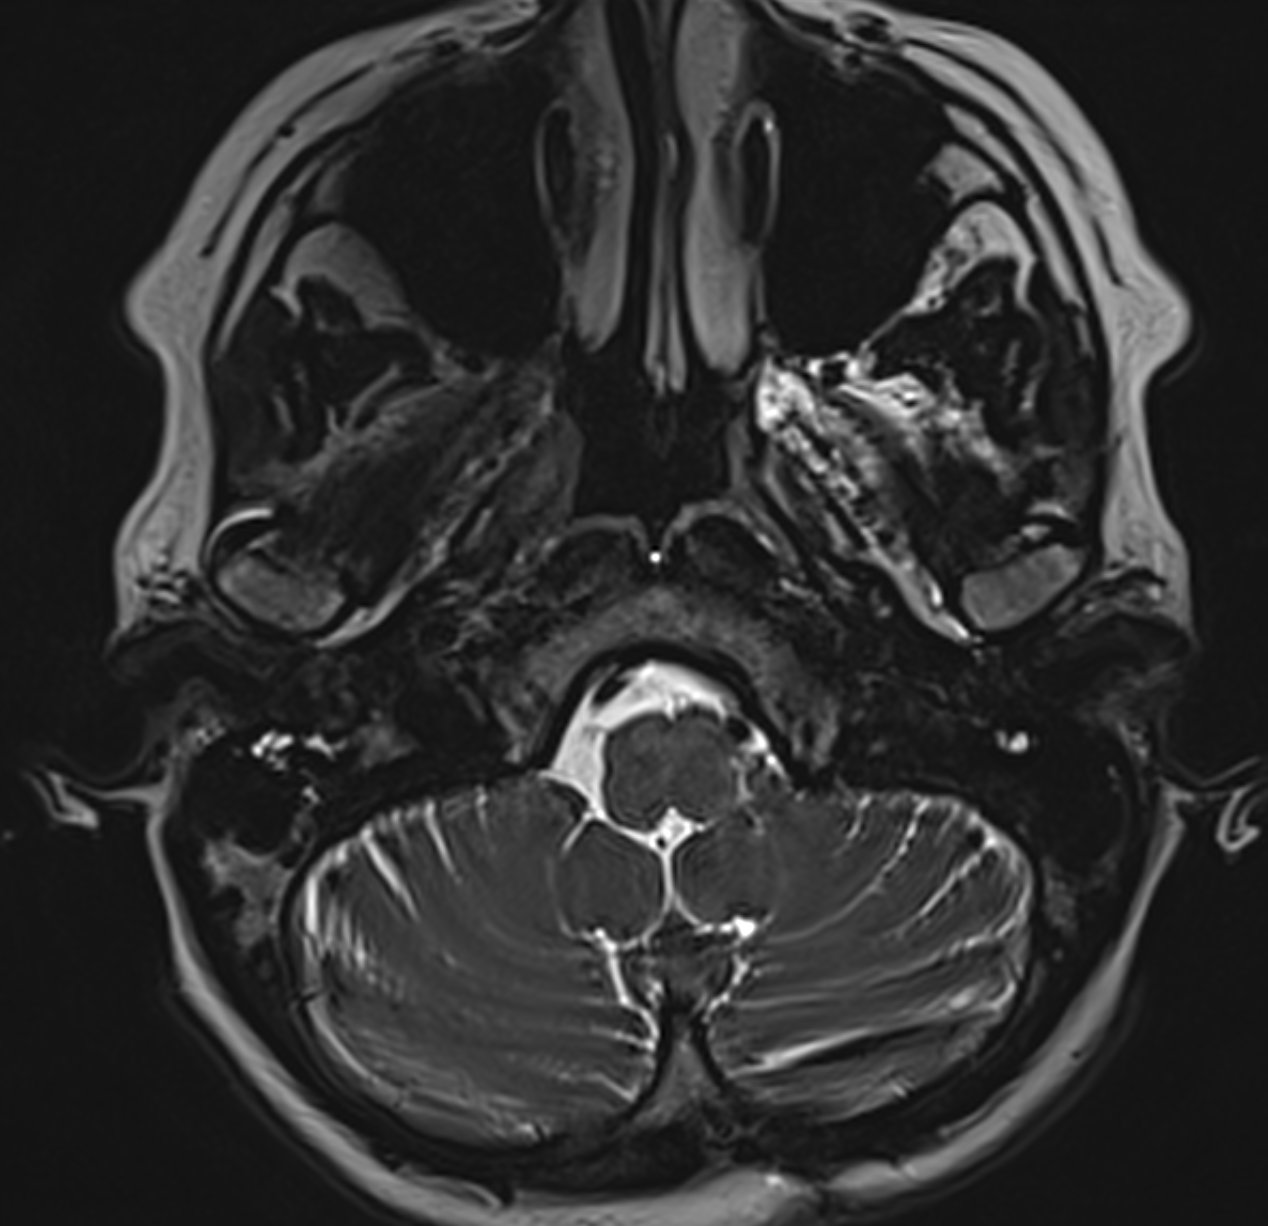

Meningiom de foramen magnum descoperit pur întâmplător Este vorba despre o doamnă de 56 ani care a efectuat un RMN...